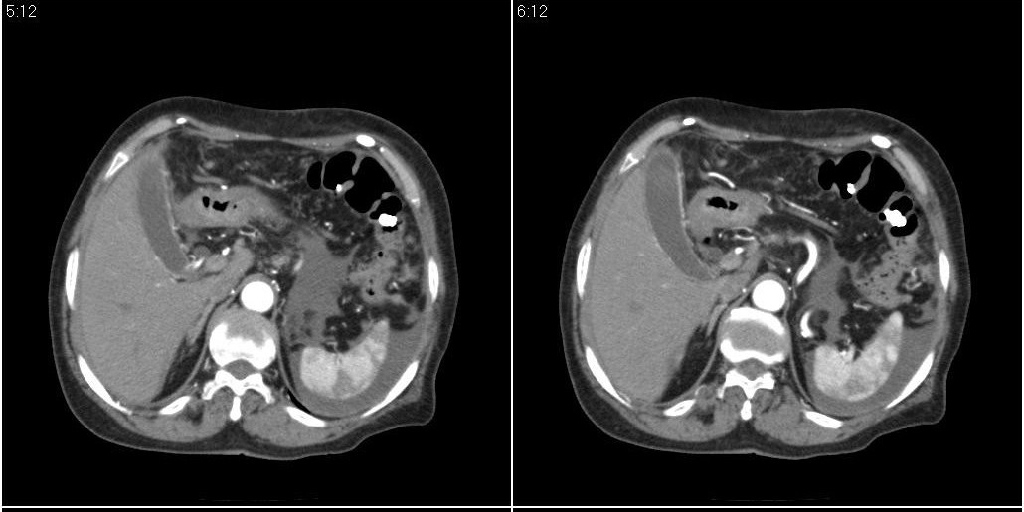

胆囊有问题么,是结石么?胆囊内异常密度平扫30hu左右,增强各期无变化。

胆囊内稍高密度影,无强化,胆囊壁增厚,周围见低密度影,右侧膈肌角及脾周水样密度,支持胆囊泥沙样结石,胆囊炎、胆囊窝积液,胸腹水。